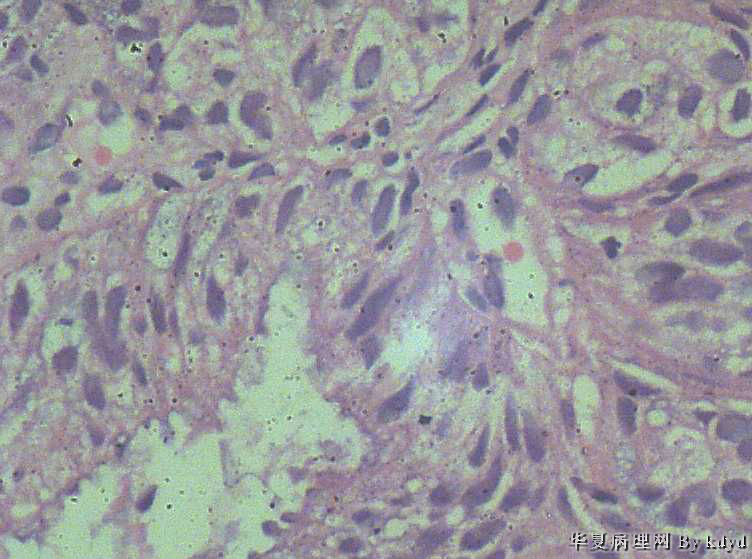

51岁,停经一年后,阴道流血。行宫腔诊刮。

B超示:宫腔有一赘生物大小1.5*2.5大小。

肉眼观:少许粘液及碎组织。(全包)

疑问:1。腺体呈复杂性增生伴不典型增生?

2。腺体有分泌反应,有些腺体看上去又像是宫颈的腺体(手术医生说是宫腔取的)?

3。怎样报告???

• 腺体非典型增生?是宫腔还是宫颈??图1

• 腺体非典型增生?是宫腔还是宫颈??图2

图2

• 腺体非典型增生?是宫腔还是宫颈??图3

图3

• 腺体非典型增生?是宫腔还是宫颈??图4

图4

腺体密集,有背靠背、共壁,有乳头状结构,有核异性性,有病理核分裂:

子宫内膜中-重度不典型增生,癌变不能排除

宫内膜样癌(高分化)。组织腺体拥挤、背靠背、血管纤维轴心乳头状,间质细胞消失代之纤维。